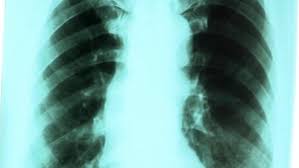

Më vonë, me paraqitjen e prezencës së gjakut në këlbazë, dhembjeve në kraharor dhe humbje në peshë, alarmohet pacienti dhe mjeku kërkon rëntgenin e mushkërive ku mund të vërehen hije të madhësisë dhe formës së ndryshme të dyshimta në kancer.

Prej këtij moment fillon intensivisht dhe në mënyrë të programuar diagnostikimi i sëmundjes si faze e parë e menaxhimit të tërësishëm të kësaj patologjie.

Bëhen ekzaminimet plotësuese rëntgenologjike (tomografia e kompjuterizuar: prerjet filmike në shtresa të kraharorit të kontrolluara me kompjuter), fiberbronkoskopia (ekzaminimi me gyp të lakueshëm në rrugët e frymëmarrjes) dhe marrja e materialit bioptik (për ekzaminim histopatologjik: në mikroskop me çka identifikohen se cilit tip dhe cilit stad i takojnë qelizat malinje).